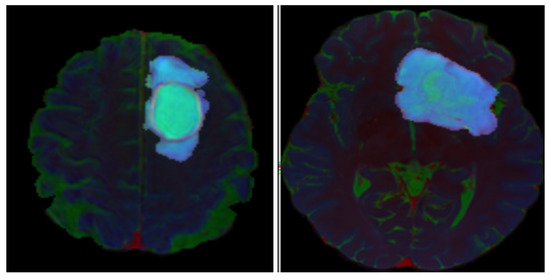

IDH Mutation Assessment in Gliomas from Anatomical MRI Using Deep Learning: A Comparative Analysis of Centralized and Federated Learning Frameworks

Background/Objectives: Isocitrate dehydrogenase (IDH) mutation is a key prognostic indicator in diffuse gliomas; however, it is clinically determined from invasive tissue sampling. Non-invasive preoperative identification of IDH mutation from routine anatomical MRI could support treatment decision making. This study evaluated deep learning models [...] Read more.

Background/Objectives: Isocitrate dehydrogenase (IDH) mutation is a key prognostic indicator in diffuse gliomas; however, it is clinically determined from invasive tissue sampling. Non-invasive preoperative identification of IDH mutation from routine anatomical MRI could support treatment decision making. This study evaluated deep learning models for IDH mutation detection using routine anatomical MRI (post-contrast T1-weighted (T1c), T2-weighted, and fluid attenuated inversion recovery (FLAIR) MRI) and quantified how tumor-focused image preprocessing and different training schemes, centralized learning (CL) versus federated learning (FL) with alternative aggregation strategies, affected model performance. Methods: Anatomical MRI from 501 diffuse glioma patients in the UCSF Preoperative Diffuse Glioma MRI (UCSF-PDGM) dataset was analyzed using a deep learning classifier built on a 2D U-Net encoder, with age and sex included as covariates. Two methods of tumor-focused image preprocessing, Naïve Soft Filtering (NSF) and Gradient-Based Soft Filtering (GBSF), were compared. Centralized learning (CL) was benchmarked against federated learning (FL) using Federated Averaging (FA) and Federated Trimmed Mean (FTM) aggregation strategies. Model performance was compared in terms of accuracy, precision, recall, F1 score, specificity, and the area under the receiver operating characteristic curve (ROC-AUC). Results: The CL model with NSF achieved the best test performance (accuracy = 0.949, F1 = 0.951, ROC-AUC = 0.971), with NSF consistently outperforming GBSF. FL’s performance decreased relative to CL’s, but the FA strategy outperformed FTM (FTM accuracy = 0.915 vs. FA accuracy = 0.949), which indicates that the FL aggregation strategy has an influence on model performance. Conclusions: Deep learning applied to routine anatomical MRI could classify IDH mutation status with high accuracy. Context-preserving image preprocessing with NSF substantially improved performance across training schemes. FL provides a privacy-preserving alternative to CL, but incurs a measurable performance degradation that is sensitive to the choice of aggregation strategy. Full article